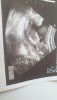

Wiesz co jesli to jest nub to co widze a nie noga to moze chlopiec,nachylenie musi byc niby wieksze niz 60 stopni od kregoslupa,ladny ma profil wygalda jakby na plazy lezal z rekami pod glowa hah

Wróżbitko Maciejko, a u mnie coś widać?

Załączniki

• 20201005_124342.jpg

20201005_124342.jpg

774,2 KB · Wyświetleń: 65